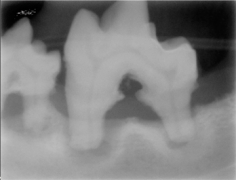

La periodontitis se clasifica como “Periodontitis leve” cuando el tejido óseo se ha destruido máximo en el tercio cervical; “Periodontitis moderada” cuando la destrucción ósea ha llegado al tercio medio de la raíz y “Periodontitis severa” cuando la destrucción ósea ha llegado al tercio apical de la raíz. La movilidad dental ligera aparece en la periodontitis moderada y la movilidad dental excesiva aparece en la periodontitis severa.